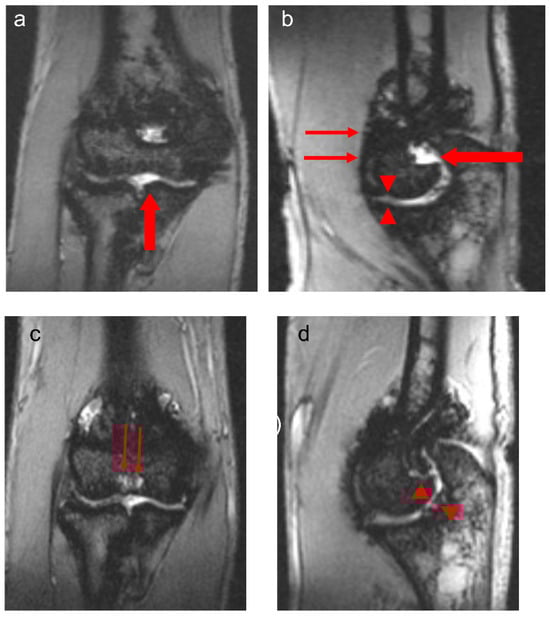

The observations in this study are of importance in the context of the assessment of blood-related arthropathy in PwH. Given that MR imaging provides the greatest detail of blood-induced damage in the structures of joints in PwH, the overall relatively strong correlations noted between the total scores derived for the four MRI scales reported in the two study arms in this communication (Table 3) are reassuring. Whereas the Denver MRI scale has progressive methodological characteristics, i.e., only the worst change for each item is scored [12], the compatible MRI scales encompass progressive and additive methodological characteristics [13]. Nevertheless, for the additive component, i.e., each grading of the item is scored, synovial hypertrophy is semi-quantitatively scored (scores, 1–3), whereas hemosiderin deposition is assessed according to the presence (score 1) or absence (score 0) of the finding. The IPSG MRI scale, in contrast, provides the ability of detailed scoring (scores, 1–3) of the soft tissue joint components (effusion/hemarthrosis, synovial hypertrophy and hemosiderin deposition) [14] which in the case of this study results was important to demonstrate interval joint changes (Figure 1 and Figure 2). Furthermore, because of its additive capability of capturing osteochondral joint changes, it enables individualized assessment of joint changes over time concerning bone erosions, subchondral cysts and cartilage deterioration, presenting with separate items for bone erosions and subchondral cysts, conversely to the methodological design concept of the compatible MRI scales in which bone erosions and subchondral cysts are grouped into a single category. The characteristics of the osteochondral domain of the IPSG scale allowed discrimination of individual osteochondral changes in the joints of patients in this study (Figure 3). For the aforementioned reasons, particularly due to its ability to provide detailed information for both soft tissue and osteochondral changes and to give approximately equal weighting to both of these domains, the 17-point IPSG additive MRI scale was used as the reference scale for the results reported in this communication [14]. Similarly, several other publications in the literature have reported the use of the 17-point scale as a reference standard in their studies [21,22,23,24,25,26,27,28,29,30].

Figure 3.

Thirteen-year-old boy with severe hemophilia A, with history of 1 prior right elbow bleed and no inhibitory antibodies. Baseline coronal (a) and sagittal (b) multiplanar gradient-recalled (MPGR) MR images of the right elbow show a small effusion/hemarthrosis (thick arrows) and superimposed marked synovial hypertrophy and hemosiderin deposition (thin arrows), and early erosive changes and cartilage loss (arrowheads, (b)). International Prophylaxis Study Group (IPSG) score = 9: soft tissue domain = 7 (effusion/hemarthrosis = 1, synovial hypertrophy = 3, hemosiderin deposition = 3); osteochondral domain = 2 (surface erosions = 1, cartilage loss = 1). Follow-up coronal (c) and sagittal (d) MPGR MR images show persistent joint cartilage loss associated with hemosiderin deposition (arrowheads, (d)). Subchondral cysts have developed in the distal humerus (thin arrows, (c)) in the interim. IPSG score = 10: soft tissue domain = 7 (effusion/hemarthrosis = 1, synovial hypertrophy = 3, hemosiderin deposition = 3); osteochondral domain = 3 (surface erosions = 1, subchondral cysts = 1, cartilage loss = 1).